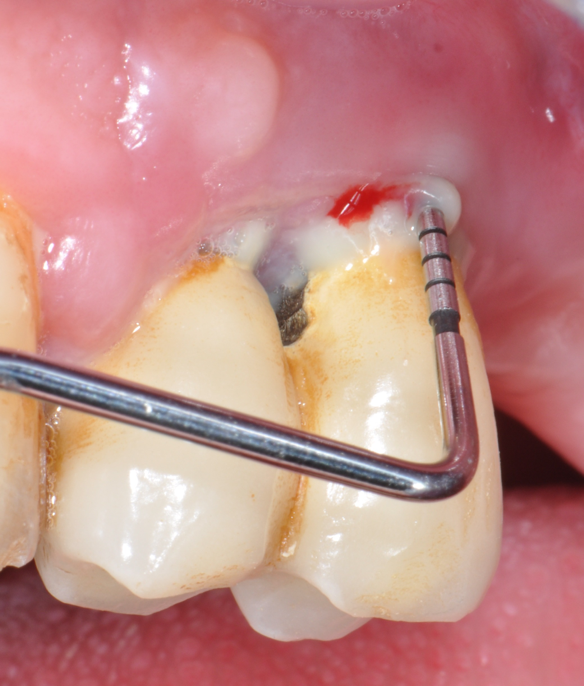

The parameters used to define peri-implant disease usually are: Probing Depth (PD), Crestal Bone Loss (CBL), Bleeding on Probing (BOP) and presence of suppuration and/or fistula.9 Peri-implant mucositis is characterised by soft tissues inflammation witnessed by BOP with or without PD deepening but no effects on the crestal bone while peri-implantitis is characterised by CBL, BOP alone or in conjunction with pus, with or without PD deepening. (Figs. 1, 2 and 3) display the diagnostic steps of a case of peri-implantitis. While mucositis allows a complete healing, peri-implantitis is not reversible.12

Fig.2: Case 1. BOP starts immediately after probing.